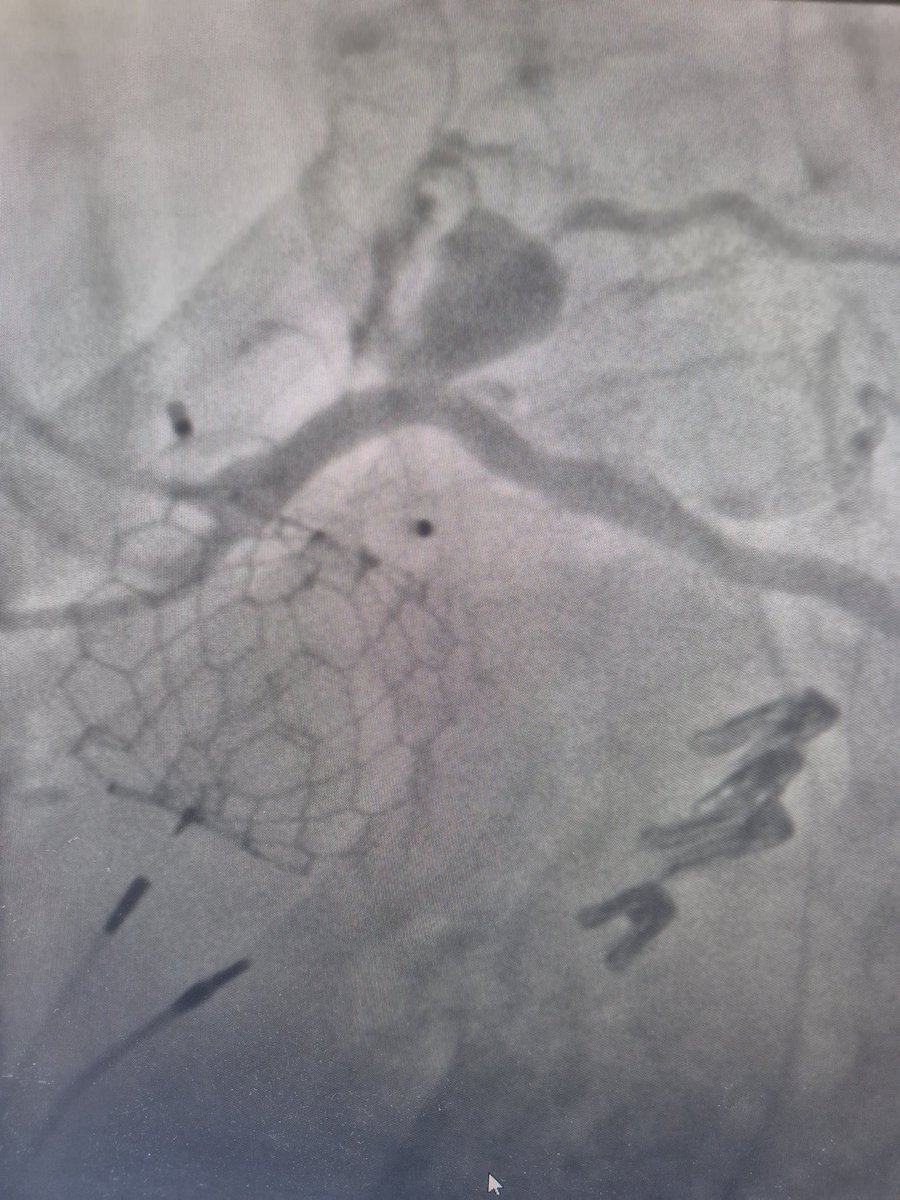

When you have ST elevation in the Inf. Leads and the culprit is the mid LAD (wrap around LAD)... With Mohammad Karmi PCRonline 🫀 @Sbrugaletta Luis Ortega Paz @Anazmicalik @guilbom Prof. Hector M. Garcia-Garcia Nicola Ryan Pascal Meier,MD @W_jyg Ignacio Cigalini 🇦🇷 Hany Ragy SABOURETCardiologist Mamas A. Mamas David J. Cohen, MD, MSc